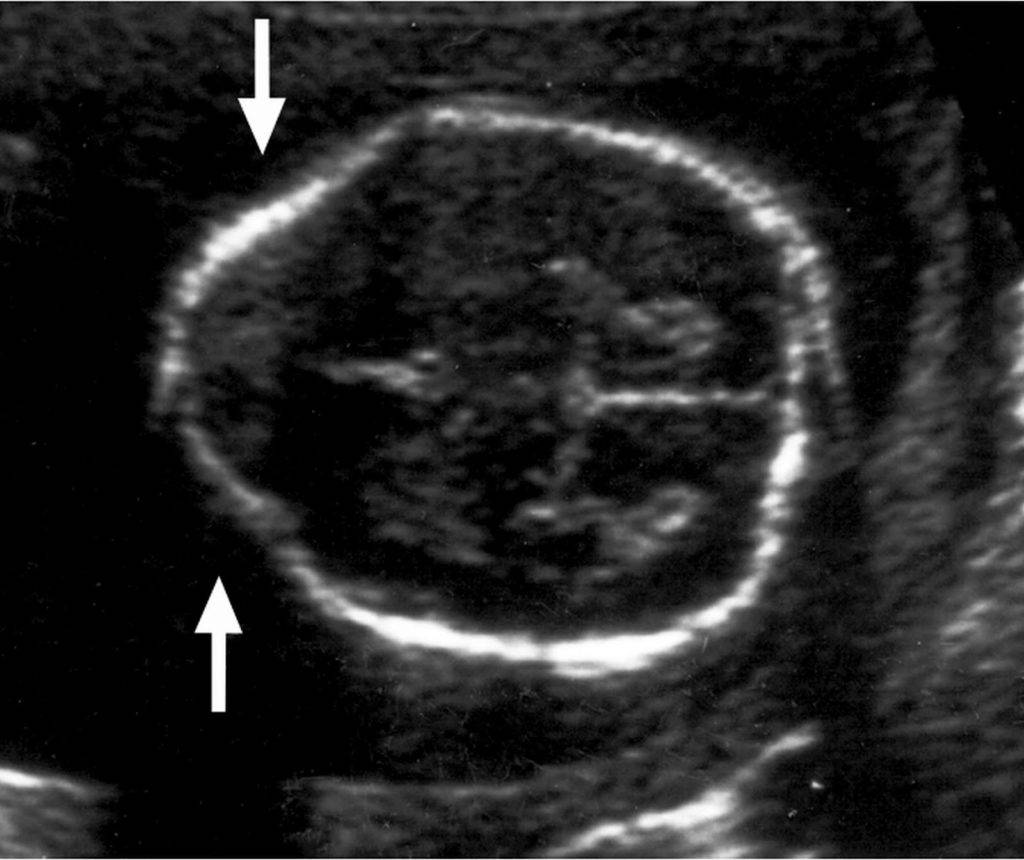

- II тип синдрома имеет врожденную форму. Прогрессирование патологии происходит во время внутриутробного развития. Аномалию можно выявить при обследовании плода. Продолговатый мозг, IV желудочек, нижний отдел червя вклиниваются на 2 мм ниже входа в большое заднее отверстие.

- Второй тип. Данная форма синдрома Арнольда-Киари развивается у плода ввиду воздействия ряда негативных факторов. Такая патология обычно проявляется у малыша практически сразу же после его рождения. В этом случае через затылочное отверстие проходит не только мозжечок – опускается также продолговатый мозг и IV желудочек. В большинстве случаев одновременно с данной патологией у пациентов выявляется врожденная спинномозговая грыжа.